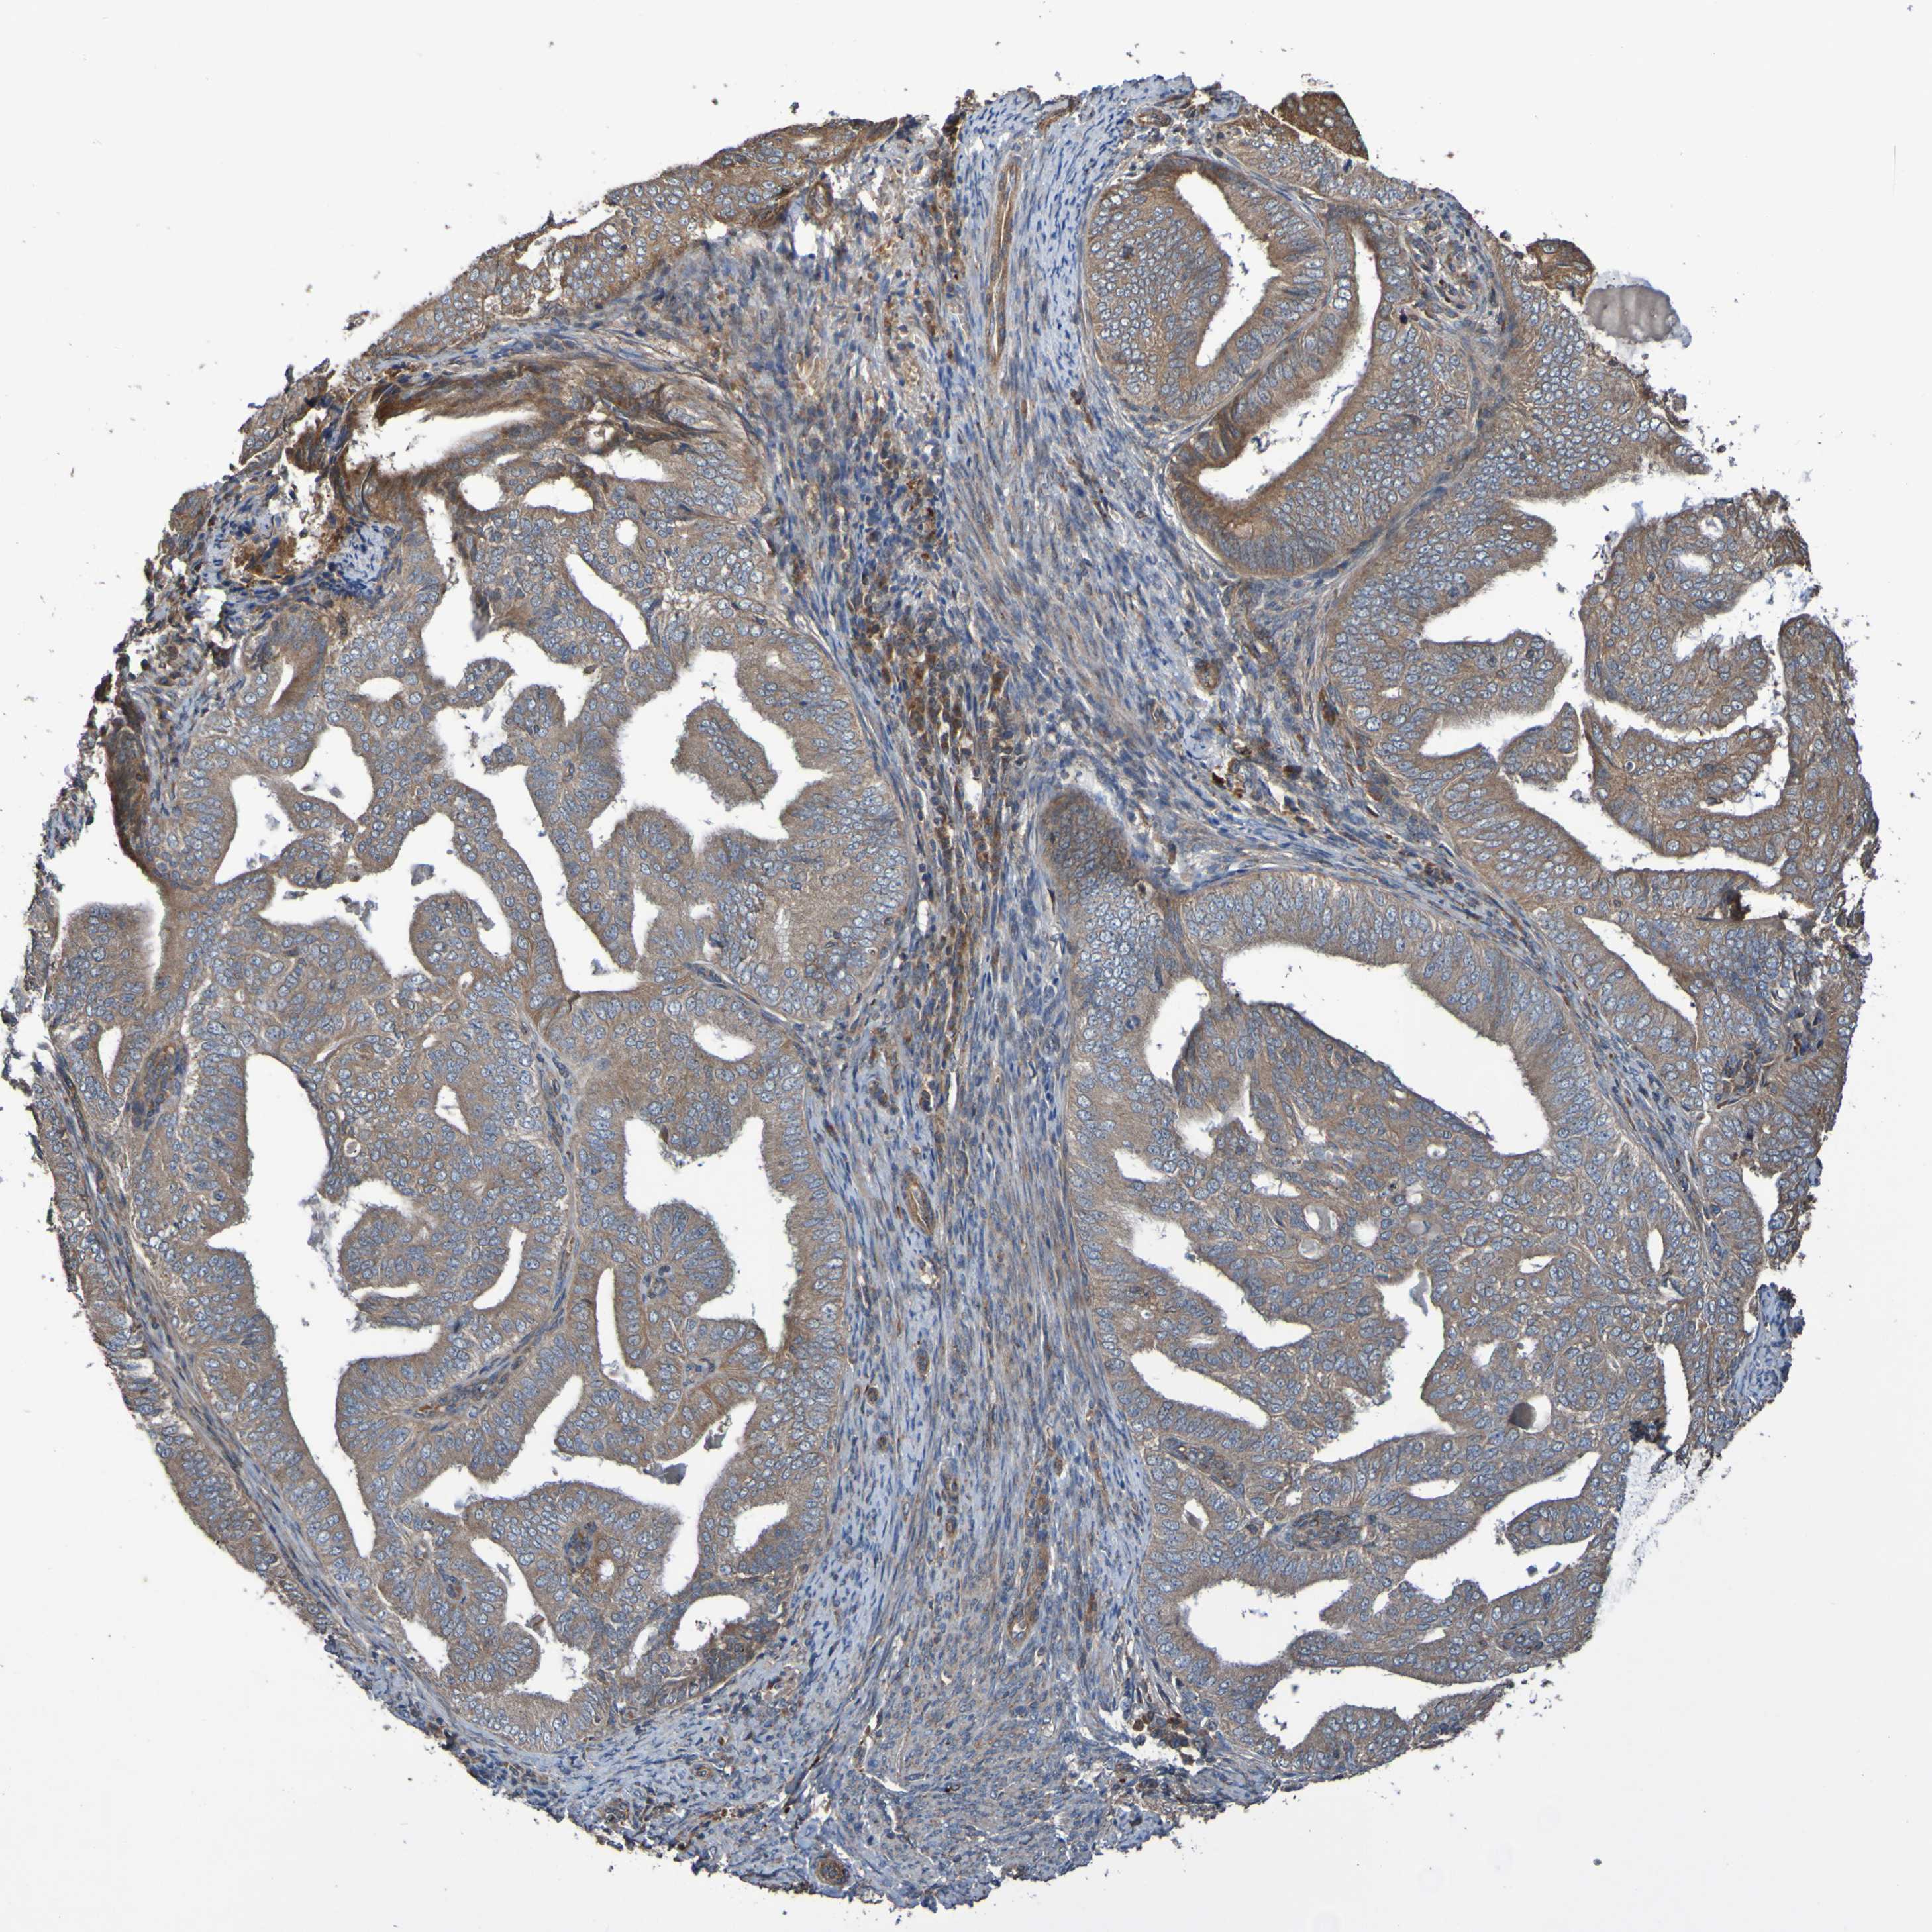

ENDOMETRIAL CANCER - Protein expressioni

A mouse-over function shows sample information and annotation data. Click on an image to view it in a full screen mode. Samples can be filtered based on level of antibody staining by selecting one or several of the following categories: high, medium, low and not detected. The assay and annotation is described here.

Note that samples used for immunohistochemistry by the Human Protein Atlas do not correspond to samples in the TCGA dataset.

Antibody stainingi

Antibody staining in the annotated cell types in the current human tissue is reported as not detected, low, medium, or high, based on conventional immunohistochemistry profiling in selected tissues. This score is based on the combination of the staining intensity and fraction of stained cells.

Each image is clickable and will lead to virtual microscopy that enables deeper exploration of all samples and also displays staining intensity scores, fraction scores and subcellular localization as well as patient and tissue information for each sample.

Antibody CAB010911

Staining

High

Medium

Low

Not detected

Intensity

Strong

Moderate

Weak

Negative

Quantity

>75%

75%-25%

<25%

None

Location

Nuclear

Cytoplasmic/membranous

Cytoplasmic/membranous,nuclear

Adenocarcinoma, NOS